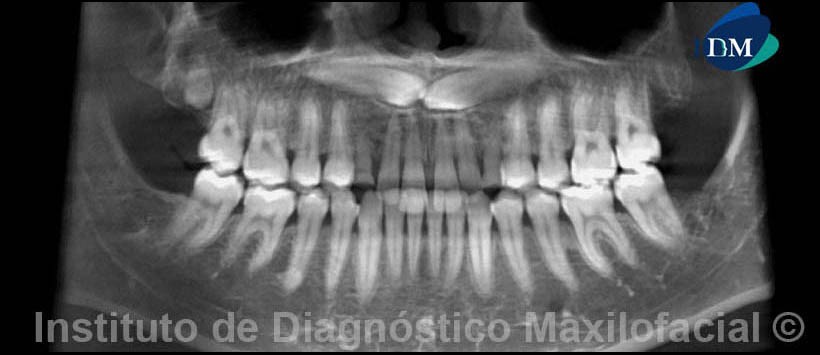

El estudio con tomografía volumétrica muestra en la reconstrucción panorámica( Fig. 1) la presencia de las piezas 1.3 y 2.3, las mismas que se encuentran impactadas entre sí.

Por otro lado, se evidencia la persistencia de las piezas 5.3 y 6.3; además de la alteración del tamaño en la pieza 1.8, compatible con microdoncia.